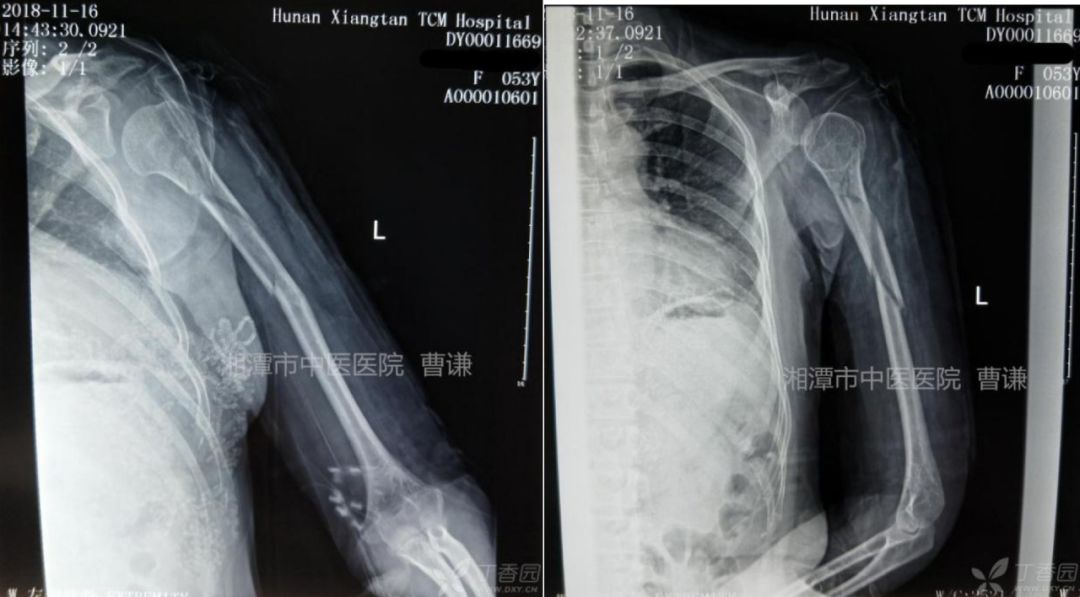

固定完成拍片复查示骨折对位对线可。

治疗一个月拍片复查,断端对位对线可,但肩关节呈半脱位改变,嘱患者加强耸肩功能锻炼,并开始肩关节被动活动。

伤后两个月复查见骨痂生长明显